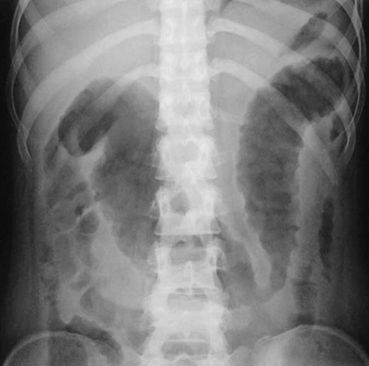

上記のような薬物療法を行っても、症状が改善せず、悪化した場合や症状が改善しない場合、十分な治療を行っても生活の質が低下した状態が続く場合などには、手術によって大腸を切除する場合があります。大量の出血、大腸の穿孔(大腸の壁が破れる)、巨大結腸症(大腸の壁が薄くなり、風船のように膨れる)などの場合は生命に関わる状態ですので、緊急で手術を行います。そのほか、発症してからおおよそ8年以上経過した方では大腸がんやその前がん病変が生じる場合があり、この場合も大腸を切除する手術が必要となります。

しかし、内視鏡的に拡張が困難な場合や腸閉塞に至った場合は、信頼できる外科医と連携し、最小限の手術で、腸管の機能を少しでも温存できるような手術を行います。術後は再手術を回避できるよう内科治療の強化や見直しを行っています。そのほか穿孔・瘻孔、腹腔内の膿瘍などの合併症が発生した際にも外科治療が必要となります。